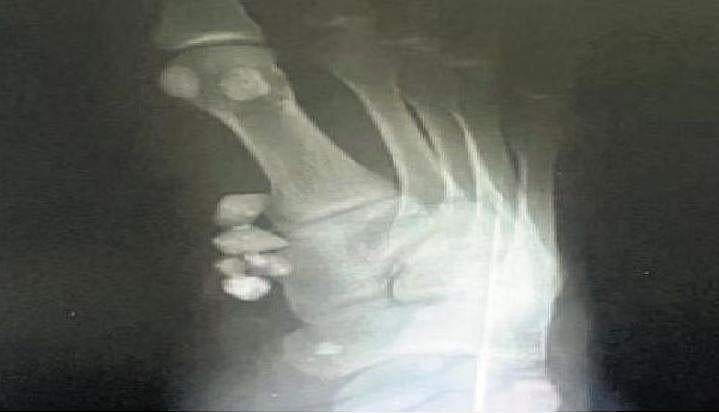

அதாவது, அவரது காலில் காயம் ஏற்பட்டபோது, தசைப் பகுதிகளுக்குள் சென்ற சிறு சிறு கற்களைக் கூட அகற்றாமல், அதனை உள்ளே வைத்து தையல் போட்டிருப்பதும், எக்ஸ்ரேவில் அந்த கற்கள் காலின் எலும்பை ஒட்டி உறவாடிக் கொண்டிருப்பதும் தெயிர வந்தது.

உரிய நேரத்தில் அந்தக் கற்களை அகற்றாவிட்டால் அது காலையே பாதித்துவிடும் என்று கூறியதை அடுத்து, உடனடியாக அறுவைசிகிச்சை மூலம் அனைத்துக் கற்களும் அகற்றப்பட்டுள்ளன. இது அந்த ஊர் முழுக்கச் செய்தியாகி, தற்போது ஊடகங்களின் வெளிச்சத்துக்கு வந்துள்ளது.